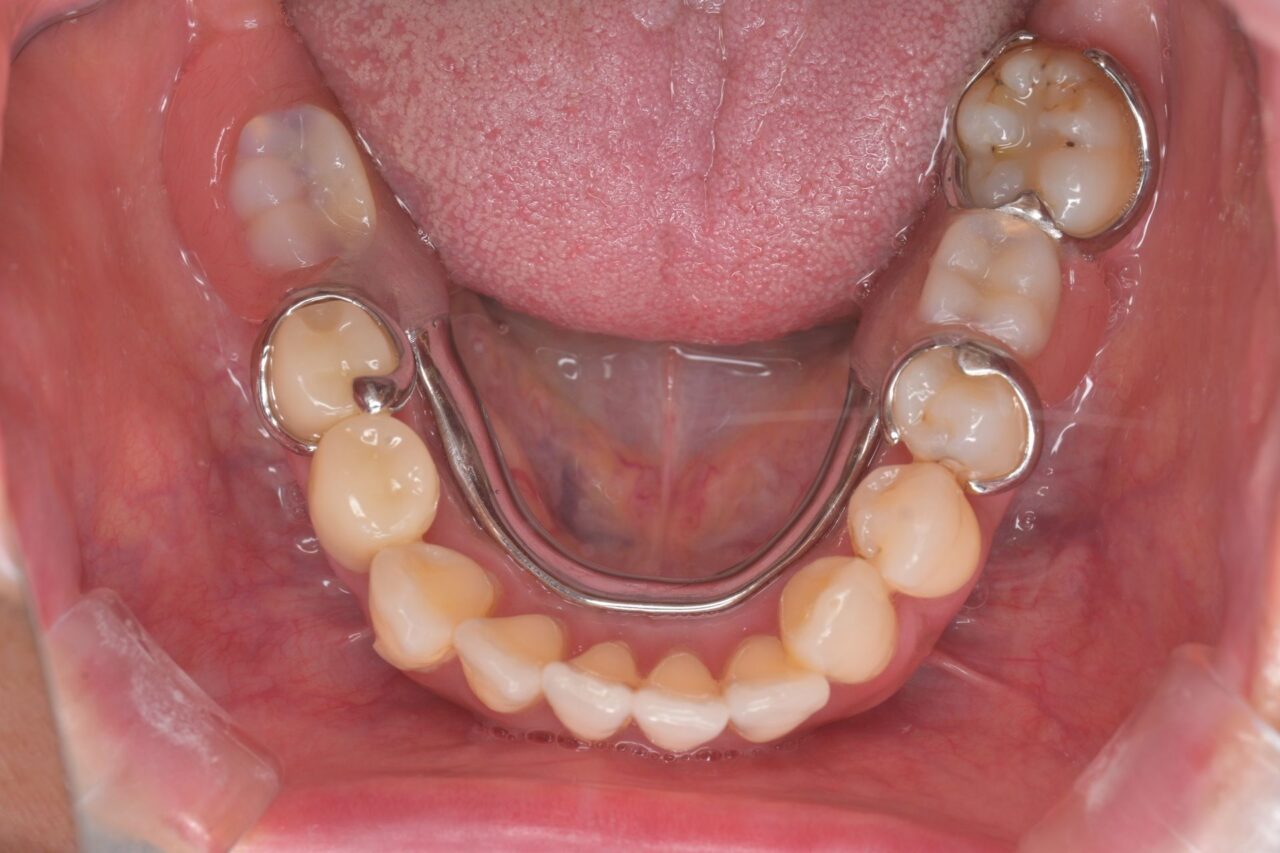

下面

歯石がたくさんついています。歯周病治療も同時に進めていきます。

親知らずも残っているので、即抜歯です。

※びわ湖大津デンタルクリニックでは、不要な親知らずは抜歯します。

親知らずは抜いて歯磨きがしやすい状況にしました。